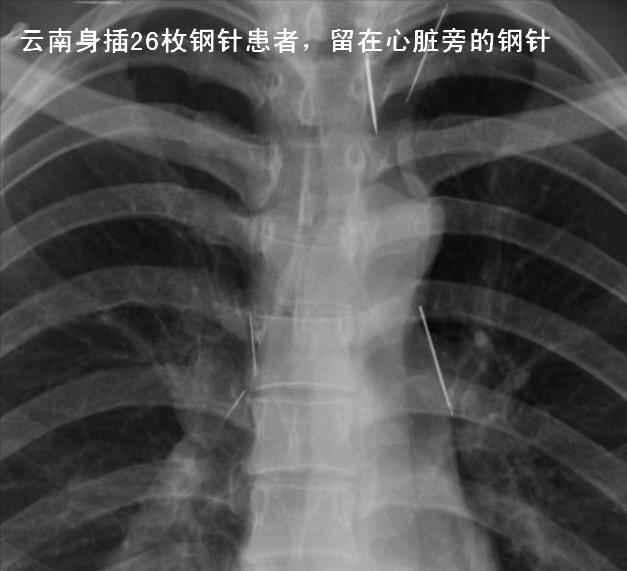

“你看,这些都是带有针孔的农家缝衣针,共有26根,分布在你的大脑、脖颈、胸腔、小腹、胯骨等地方。”

罗翠芬体内的钢针

医生的表情越来越凝重,继续说:“有几根针存在的位置比较特殊。比如,有根针直插大脑,有根针离脖子的大动脉很近,还有一根针位于离心脏很近的位置。这些针只要再移动个几厘米,就会危及生命。”

罗翠芬体内心脏旁的钢针